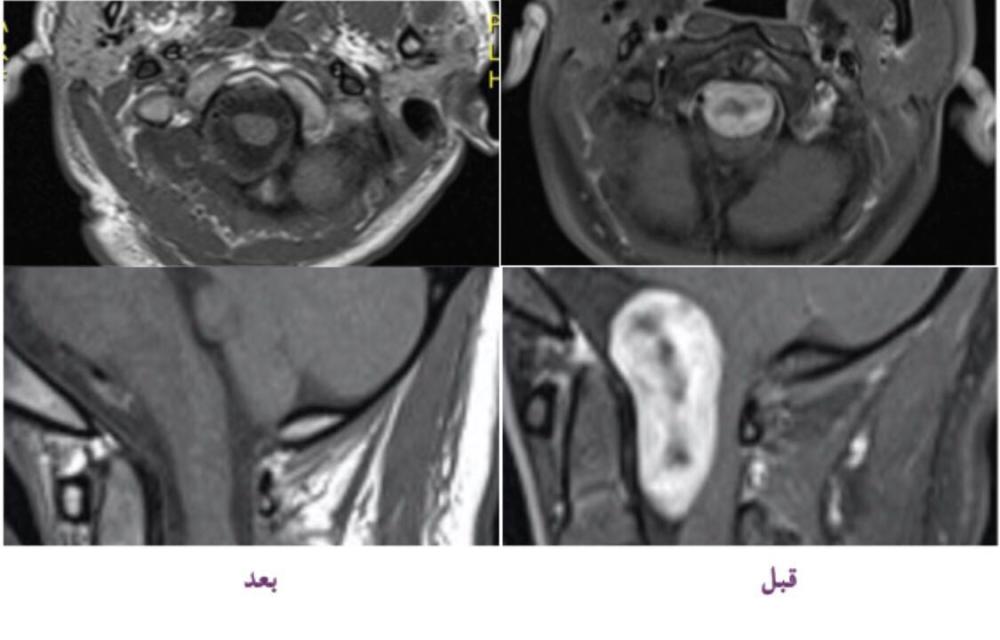

وأشار الصيعري، إلى أنه بفضل من الله، تم عمل أشعة دماغية لها بعد العملية، وبينت الأشعة إزالة الورم بالكامل، والآن المريضة تتماثل للشفاء وهي بصحة جيدة وبدأت بالمشي والحركة، وتحتاج فقط إلى العلاج الطبيعي ليتم شفاؤها بإذن الله.